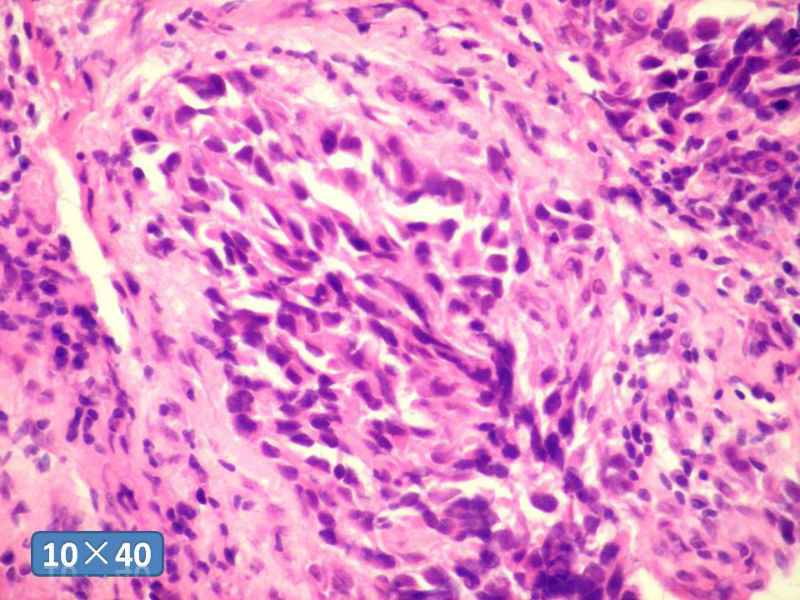

女性,50岁,乳腺肿物,冰冻切片(图1-25)

HE